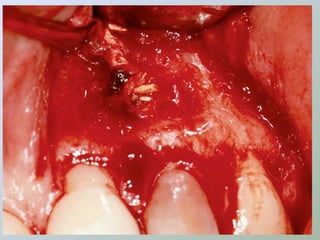

Acesso ao

Acesso ao periápice

• Freqüentemente o

osso cortical sobre o

ápice é reabsorvido

expondo uma lesão de

tecido mole

• Ampliar a abertura óssea

• Cinzel

• Broca esférica cirúrgica

• Expor a raiz e boa parte da

lesão

• Irrigação abundante

• Solução fisiológica

• Exposição óssea suficiente

para permitir boa visualização